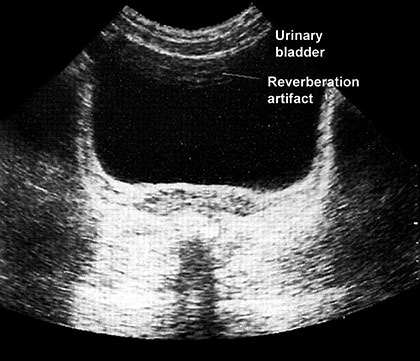

Reverberation occurs between transducer and a strong reflector or it can occur between two reflecting surfaces lying in the direction of beam. Here the reflector may be sufficiently strong to be detected by the instrument and to cause confusion on the display. The process by which they are produced is explained in Figure 1.21A. This result in the display of reflector that are not real.

Therefore not all echoes that originates at an acoustic interface return to the transducers without further reflection. If strongly reflecting boundaries are present sound wave can reflects back and forth before they eventually return to the transducer. This delay in registering the echo leads to reverberation. These reverberation echoes are projected as several parallel line placed beneath the real reflector at separate interval equal to separation between the transducer and real structure. And each subsequent echo is weaker than prior one, e.g. from intestinal gas to liver or ribs, urinary bladder or gallbladder. Reverberation can obscure tissue that lie behind the gas (Fig. 1.21B).

Fig. 1.21B: Echoes seen in the anterior portion of the urinary bladder due to reverberation artifacts